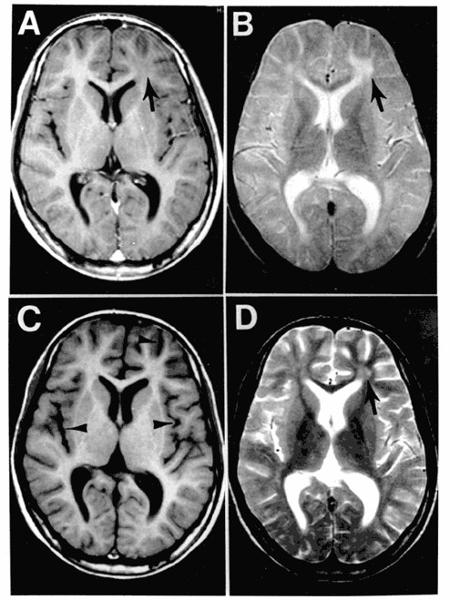

what is going on here

hydrocephalus

what is this aqueductal stenosis causing

hydrocephalus on MRI

what space would be more dilated: space after aqueductal stenosis or before it

before

what type of imaging is this and what is being shown

MRI: water dense in MRI

arrow poniting to periventricular damage, which is more likely with high pressure hydrocephalus